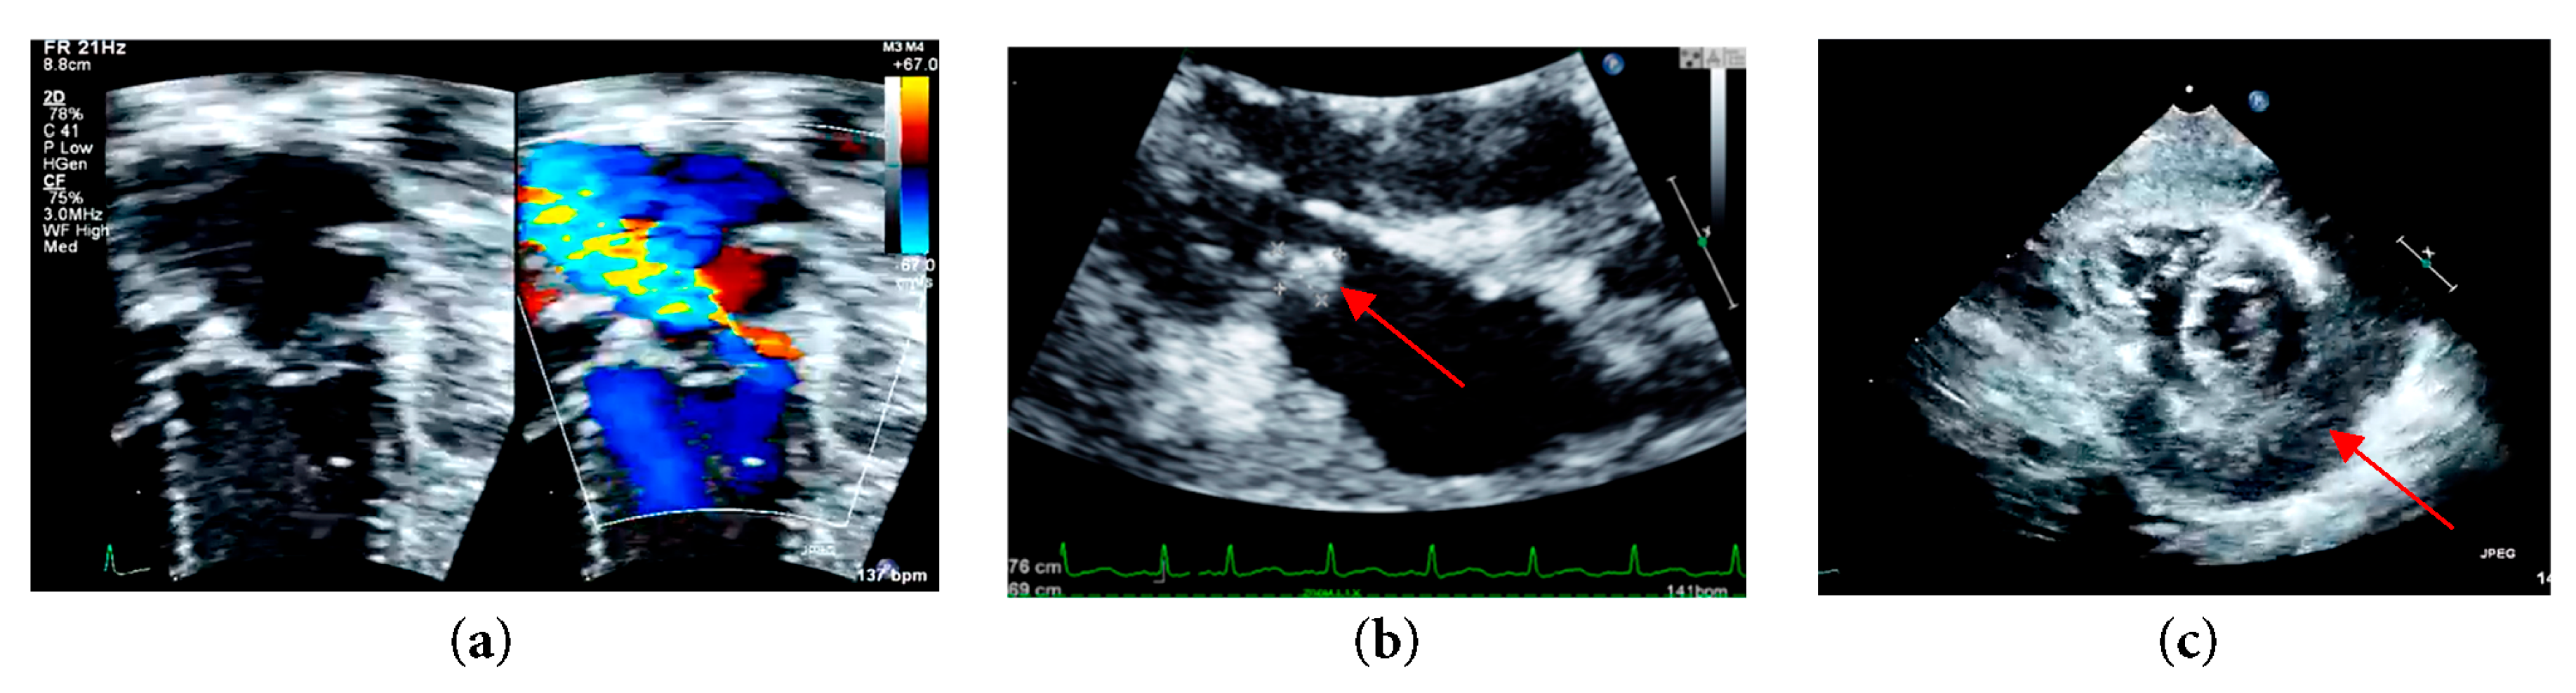

Upon stabilization, her blood pressure was 88/40 mmHg, and her heart rate is 140 beats per minute with an oxygen saturation of 100%. Both cardiovascular and respiratory examinations were normal. The abdomen was soft. Full blood count showed increased white cell count and platelet count at 19.1 × 109/L and 523 × 109/L, respectively. C-reactive protein (CRP) was also raised at 210.9 mg/L. Otherwise, blood, tracheal and urine culture and sensitivity show no growth. An electrocardiogram was done showing sinus rhythm, and normal axis deviation but ST elevation was seen at lead II, III, AVF, V3–V6, consistent with pericarditis. Bedside echocardiogram reveals moderate mitral regurgitation with vegetation of 5 × 7 mm seen at the posterior mitral valve annulus. The left atrium and left ventricle were dilated with a left ventricular ejection fraction of 68%. Global pericardial empyema of 10 to 14 mm was seen (Fig. 1).

Figure 1: (a) Left apical four chamber echocardiographic view with color Doppler at the level of mitral valve demonstrating moderate mitral regurgitation; (b) Parasternal long axis echocardiographic view demonstrating mitral valve vegetation; (c) Parasternal short axis echocardiographic view at mid papillary level demonstrating a global pericardial empyema.